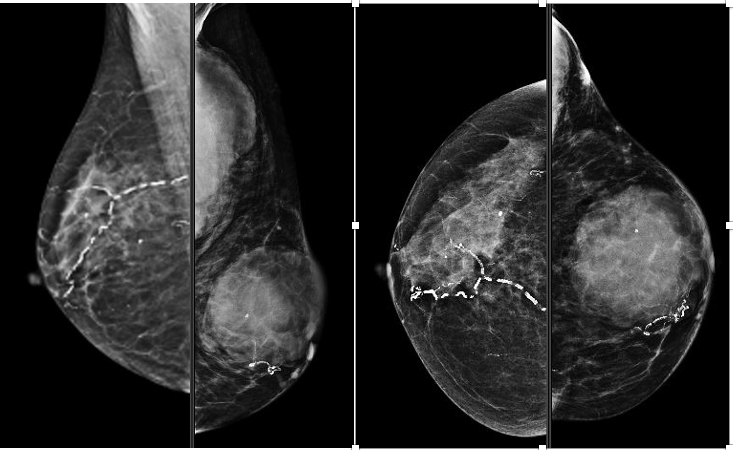

Mammography (Figure 1)revealed a large, round, well circumscribed, high density mass in upper outer quadrant and central region, measuring 7 x 6 cm. No suspicious calcification, architectural distortion, nipple retraction, skin or nipple-areolar thickening was seen. Associated was a large node measuring 11 x 9 cm noted in the left axillary region. Right breast and axilla were unremarkable. Correlation USG images were not available on Electronic Medical Record and PACS system, hence not available for reproduction here, however, as per the report, it appeared as a lobulated hypoechoic mass in left breast with necrotic changes, and internal vascularity in the solid component. Similar morphology additional left axillary mass was also seen. Imaging features highlighted the absence of spiculation, calcification, architectural distortion, irregular margins. The mass was categorized as BIRADS 4c, with a high probability of malignancy.Differentials on basis of mammography and USG were triple negative breast carcinoma, phyllodes tumor, cellular fibroepithelial lesion, organized abscess, lymphoma or metastases. CT was done to see disease extent which revealed a heterogeneously enhancing left breast mass (Fig 2a), large axillary and retropectoral adenopathy. No other adenopathy or abnormality seen. Biopsy from the breast lump was performed which showed Non-Hodgkin’s lymphoma of diffuse large B cell type, positive for CD20 and Mum1 which are markers of mature B cells. CSF study and Bone marrow aspiration were negative for involvement by disease. Diagnosis of primary breast lymphoma was made and planned for chemotherapy R-CEOP (rituximab, cyclophosphamide, etoposide, vincristine and prednisone) followed by IFRT (Involved field radiotherapy). Post 3 cycles of chemotherapy, FDG PET (Fig 2b and 3a) was done which showed significant reduction in size of breast mass and axillary node, breast mass then measuring 2 x 2cm with SUVmax of 7 while the axillary node measured 3.4 x 2.6 cm with SUV max of 3.7. Another repeat FDG PET Scan (Fig 2c and 3b)was done after completion of chemotherapy for further response assessment which showed no FDG uptake in left breast lesion suggesting complete metabolic response however size of the lesion appeared nearly stable, as compared to previous FDG PET (performed in the interim period of therapy). Patient has a 2-year disease free interval, and has not visited due to the Covid pandemic situation, but on telephonic follow up, is asymptomatic with good performance status. Figure 4: Low power (a), High power (b) and CD20 staining (c) from another case of primary breast lymphoma. These are representative images added here for teaching purpose. Figure 2a (10x power) shows diffuse infiltration by malignant cells. Figure 2b shows monomorphic round cells with apoptosis. Figure 2c staining positive for phenotype analysis for B cells. Representative USG image (Figure 5 and 6) of different patients with biopsy proven B cell lymphoma with different demographics. (Figure 5) USG of breast lump in a 56 year old woman shows hypoechoic, round mass, circumscribed margin with posterior acoustic enhancement mimicking a receptor negative carcinoma, mucinous carcinoma or fibroepithelial lesion. (Fig 6) Large mass in a 21 years old lady shows mixed echogenicity oval mass of parallel orientation, with well circumscribed margin and surrounding echogenic rim due to edema, mimicking a phylloides tumour, a fibroepithelial lesion or a malignant etiology.